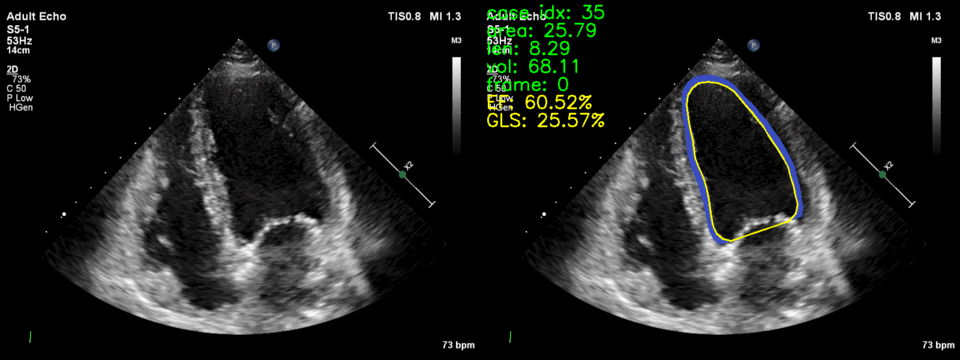

Phương pháp do TS. Trần Quốc Long và nhóm nghiên cứu đề xuất thuộc dự án “AI-Cardio: Hệ thống trí tuệ nhân tạo chẩn đoán và tiên lượng bệnh nhồi máu cơ tim dựa trên siêu âm tim”. Dự án dựa trên siêu âm tim mang đến khả năng tính toán tự động một số chỉ số quan trọng chỉ báo sức khỏe của quả tim như phân suất tống máu, sức căng toàn thể theo chiều dọc tâm thất trái. Trên cơ sở đó, phần mềm hỗ trợ các bác sĩ chẩn đoán, tiên lượng bệnh nhồi máu cơ tim dựa trên siêu âm tim.

Các thuật toán tự động phân tích hình ảnh siêu âm tim sử dụng các phương pháp Trí tuệ nhân tạo mới nhất, cụ thể là các phương pháp nhận dạng hình ảnh dựa trên kỹ thuật học sâu, được nhóm nghiên cứu phát triển để nhận dạng hình ảnh động theo nhịp đập của quả tim. Để các thuật toán hoạt động chính xác, các bác sĩ đã kỳ công gán nhãn để tạo bộ dữ liệu cho hàng nghìn ca siêu âm tim, trên các loại máy siêu âm tim khác nhau. Dựa trên kết quả nhận dạng, phân tích ảnh siêu âm, phần mềm tự động ước lượng các chỉ số quan trọng của quả tim cho phép chẩn đoán, tiên lượng bệnh nhồi máu cơ tim. Với cách tiếp cận này, dự án tự động hóa một số chức năng còn phải thực hành thủ công hoặc bán tự động trên máy siêu âm tim, cần bác sĩ có chuyên môn kỹ thuật tốt và hiện nay khá đắt đỏ. Tính năng tự động này giúp các bệnh viện tuyến dưới sàng lọc bệnh nhân nhồi máu cơ tim tim tốt và hiệu quả hơn.

Hình 3 cho đánh giá định tính về chất lượng hình ảnh được tạo. Phương pháp đề xuất tổng hợp hiệu quả các hình ảnh siêu âm tim với chuyển động thực tế của vùng thất trái (LV), tuân thủ theo cấu trúc của bản đồ phân vùng. CDM gặp khó khăn trong việc duy trì cấu trúc giải phẫu nhất quán, đặc biệt là ở các khu vực có hiện tượng và biến dạng như vùng hình nón. Nguyên nhân có thể là do bản đồ phân vùng chỉ chứa vùng LV, gây khó khăn cho CDM trong việc tạo ra các đại diện đồng nhất. Việc sử dụng nhãn giả trong các khu vực này giúp khắc phục vấn đề, đảm bảo tính nhất quán trong các hình dạng siêu âm được tạo ra. Cách tiếp cận này cho thấy triển vọng trong việc xử lý sự biến đổi và phức tạp vốn có của dữ liệu siêu âm tim, như đã thấy trong các hình dạng đa dạng của các bộ dữ liệu siêu âm tim.

Phương pháp đề xuất là một mô hình khuếch tán video có điều kiện không cần đào tạo (CDM) cho việc tổng hợp siêu âm tim. Phương pháp này có thể tạo ra các hình ảnh siêu âm tim thực tế từ một bản đồ phân vùng cuối kỳ tâm trương duy nhất. Hiệu quả của mô hình trên hai bộ dữ liệu công khai CAMUS và EchoNet-Dynamic cho thấy mô hình đạt hiệu suất tốt về chất lượng hình ảnh cả định lượng và định tính. Thông qua các thí nghiệm, mô hình đề xuất có thể tạo ra các hình ảnh siêu âm tim tốt, đồng nhất theo thời gian và phù hợp về mặt không gian với bản đồ phân vùng đầu vào mà không cần dữ liệu đào tạo bổ sung. Cách tiếp cận này mở ra những khả năng mới cho việc tạo ra các hình ảnh siêu âm tim từ một bản đồ phân vùng duy nhất, có thể được sử dụng cho tăng cường dữ liệu, thích ứng miền và các ứng dụng khác trong lĩnh vực hình ảnh y tế.